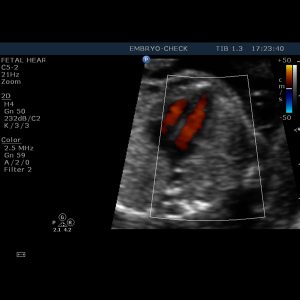

Η EMBRYOCHECK είναι εξειδικευμένη σύγχρονη μονάδα εμβρυομητρικής ιατρικής και εμβρυϊκής καρδιολογίας, αφιερωμένη στην υγεία της γυναίκας – μητέρας και του εμβρύου της και μελλοντικού παιδιού της. Ιδρύθηκε το 2006 και παρέχει υπηρεσίες που καλύπτουν όλο το φάσμα υπερηχογραφικής απεικόνισης στην μαιευτική και γυναικολογία. Βρίσκεται στο κέντρο της Αθήνας έναντι του Μεγάρου Μουσικής.